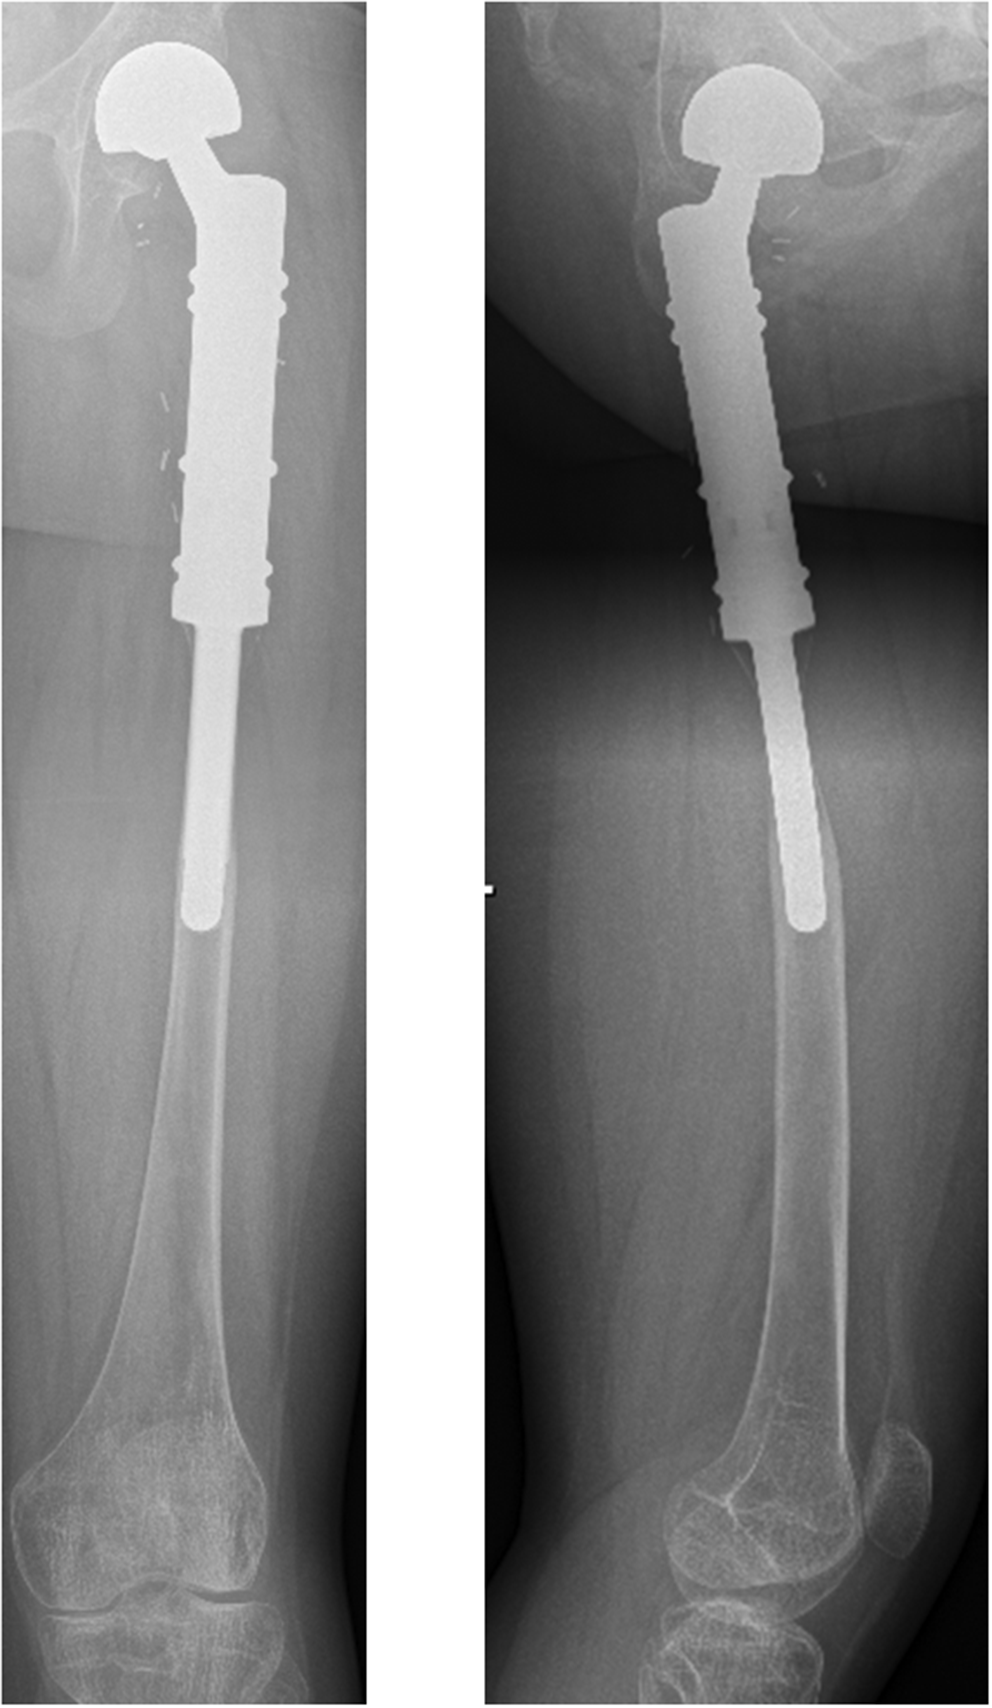

Stress shielding

Stress shielding describes the asymptomatic degeneration of cortical bone adjacent to cementless prosthetic implant stems in pediatric populations. It was observed in ten patients of this cohort (n = 10/14; 71.4%) (Fig. 1). Only patients #5 and 9 (reconstructed using hollow custom-made short stems) and patients #11 and 12 (aged 16 and 17 years) were not affected by stress shielding.

Fig. 1

11-year-old patient (#2) with a Ewing’s sarcoma of the left proximal femur. A.p. and lateral x-rays 52 months after the operation (patient age 16 years) with presentation of significant stress shielding in both planes